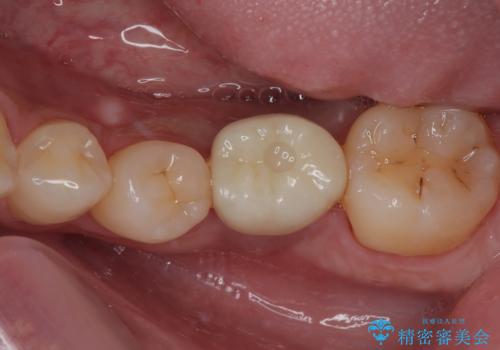

理想的な咬み合わせに改善した上で、インプラント補綴治療を行うこととしました。

部分矯正を行ったこと治療期間は長くなりましたが、違和感のない咬み合わせを達成することができました。